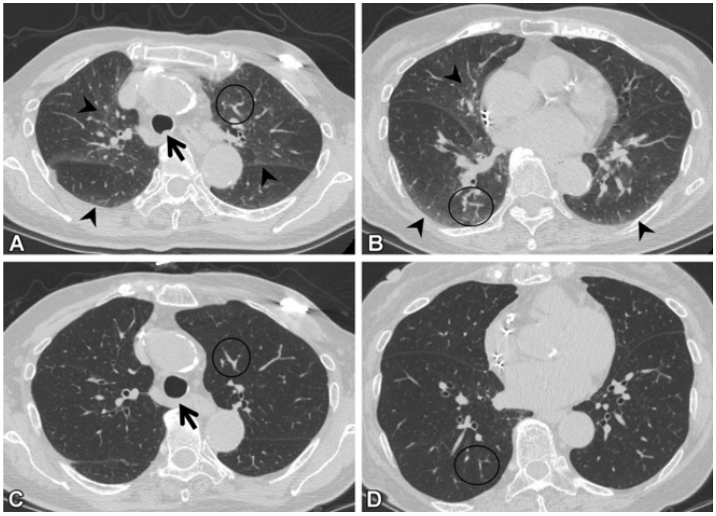

(1)感染性疾病:病毒性?细菌性?真菌?非典型病原体?吸入性肺炎?(2)非感染性疾病:心衰?急性肺栓塞?自身免疫性疾病?麻醉/手术相关肺损伤?急性间质性肺炎?回顾分析患者入院时胸部CT: 双肺靠近外周近胸膜处有轻微细小间质样改变(图4)。诊断:急性间质性肺炎;Ⅰ型呼吸衰竭;左肺下叶部分切除术后;高血压病。ECMO支持;呼吸机支持;甲泼尼松80 mg q12h,尼达尼布;镇静镇痛;抗感染;营养支持。ECMO第6天, 术后第18天, 肺部病变进一步加重(图5)。血气分析: pH 7.543, PaO2 154 mmHg, PaCO2 33.2 mmHg(ECMO, FiO2 100%, MV FiO2 60%)。术后第26天复查胸部CT未见改善。患者最终死亡。笔者团队也曾接诊过一例早期肺癌患者,2013年和2014年随访肺部结节均无明显变化。2015年胸部手术后2天,两肺变白(图6)。当时医生警惕性非常高,立刻行胸部CT检查并予相应治疗,患者最终存活。2022年RadioGraphics 杂志报道一例85岁女性腺癌患者奥希替尼治疗5个月后。图7-A和B为治疗前胸部CT图像,可见右肺中叶有肿块(A中箭头)。胸膜下区域磨玻璃改变和网状结构(箭头)提示存在间质性肺异常(Interstitial Lung Abnormalities,ILA)。治疗5个月后的轴位CT图像显示肿块(C中白色箭头)、弥漫性磨玻璃改变和合并症(黑色箭头)。图源:Radiographics, 2022, 42(7):1925-1939.另一例66岁右上肺鳞癌患者,术前CT显示肿块(图8-A中箭头)位于肺右上叶。轻度磨玻璃改变(箭头),提示ILA,见于胸膜下区域。图8-C和D为术后CT,显示弥漫性磨玻璃样改变和实变(箭头),牵引性支气管扩张症(图8-C中箭头),也可见胸腔积液(图8-D中箭头)。图源:Radiographics, 2022, 42(7):1925-1939.